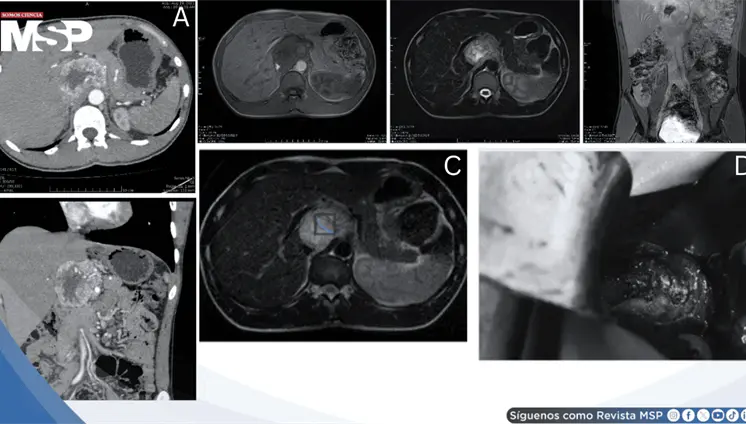

Lo que comenzó como un cuadro frecuente de dolor pélvico y dismenorrea en una mujer, terminó siendo un carcinoma folicular originado en estruma ovárico maligno. La paciente tenía solo 35 años, marcadores tumorales completamente normales y ninguna alteración tiroidea.